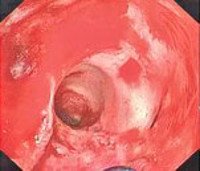

При отсутствии заболеваний заднего прохода перианальная зона в первые дни болезни не изменена. В последующем из-за зияния сфинктера у больных язвенным проктитом может выявляться загрязнение кожи калом, кровью, гноем и слизью с развитием мацерации. Ректальное исследование подтверждает наличие отека прямой кишки. Наиболее информативной методикой при язвенном проктите является ректороманоскопия, позволяющая визуально оценить выраженность и распространенность воспаления, количество, размеры и глубину язв. При проведении эндоскопического исследования осуществляют биопсию. Для определения причин развития язвенного проктита назначают копрограмму, анализы кала на бакпосев и на яйца глист. При подозрении на специфическую инфекцию (гонорею, сифилис) пациента направляют на консультацию к венерологу.

Язвенный проктит. Тяжелая форма воспаления прямой кишки, характеризующаяся образованием язв на слизистой оболочке. После заживления язв формируются рубцы, способные становиться причиной развития стеноза прямой кишки. Проявляется гипертермией, нарушением общего состояния, тенезмами, болью, зудом, жжением, выделением крови, гноя и слизи с каловыми массами. Язвенный проктит диагностируется с учетом клинических проявлений, данных осмотра, ректального исследования, эндоскопии, биопсии и других диагностических методов. Лечение консервативное, включает в себя диету, клизмы, ванночки, общую и местную медикаментозную терапию.